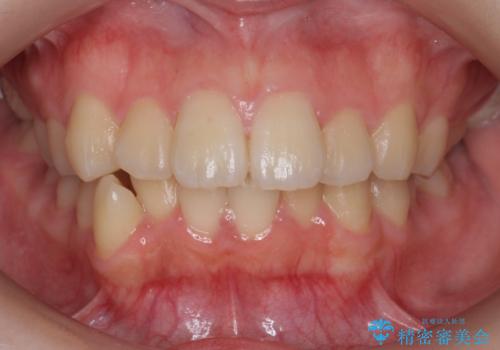

[40代女性] 口元を引っ込めたい 大きく改善

当院に来る前は、某美容外科の歯科で、上下前歯をかぶせて200万と言われたとのことでした。

それでは前歯の位置は変わらず、健康な歯を削って形が多少変わるだけで口元も引っ込みません。

下の歯槽骨が薄くリスクもありましたが、結果矯正治療をして、かぶせ物よりも効果のある治療ができたと自負しています。

![[40代女性] 口元を引っ込めたい 大きく改善の治療後](https://seimitsushinbi.jp/wp/wp-content/uploads/2018/01/C1071-500x350.jpg)